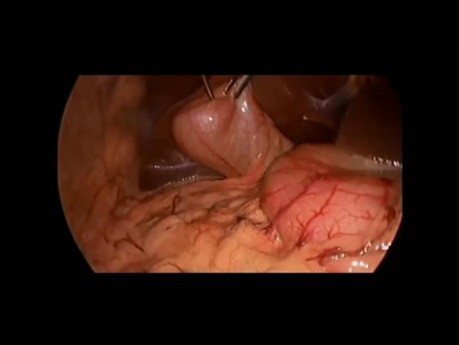

Reparación laparoscópica de hernia inguinal (TAPP)....

La hernia inguinal es una condición muy común que puede requerir cirugía laparoscópica. Este video es una demostración paso a paso de la hernioplastia laparoscópica con malla.